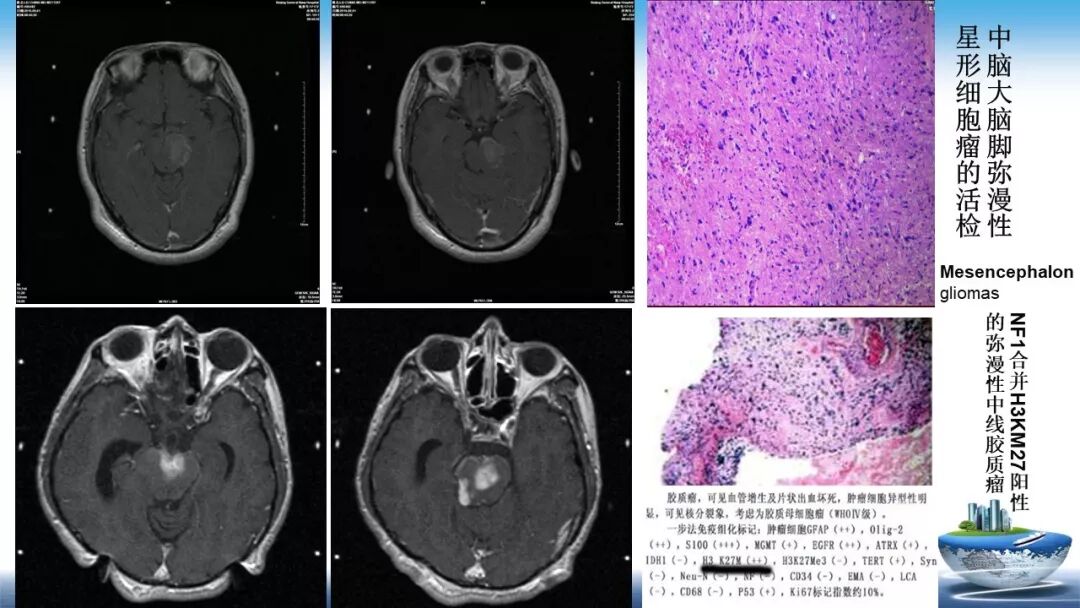

立体定向活检在脑干中线病变精准诊断中的作用

今天为大家带来的是中国人民解放军总医院第六医学中心(原中国人民解放军海军总医院)王亚明、于新、张剑宁带来的精彩课题分享:立体定向活检在脑干中线病变精准诊断中的作用,欢迎观看、阅读!